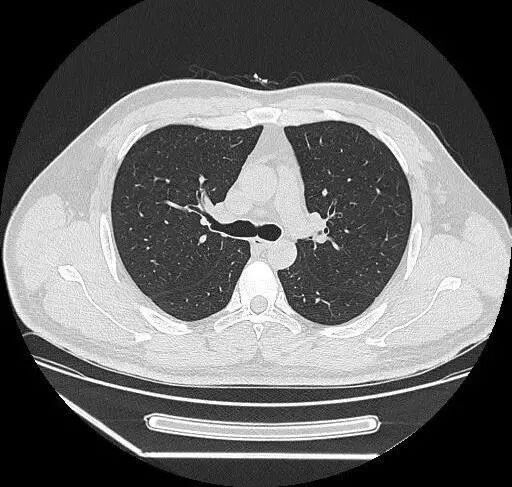

这么说吧,X光片就是把人压扁了看,超声就像挑西瓜前敲一敲,核磁共振则是摇一摇再看,而CT,厉害了,把人切成一片一片仔细看。

而且这个切片厚度<1mm。

胸部:

肺、胸膜及纵隔的各种肿瘤、结核、炎症、支气管扩张、肺脓肿、肺不张、气胸、骨折、食道异物及各种变异等;